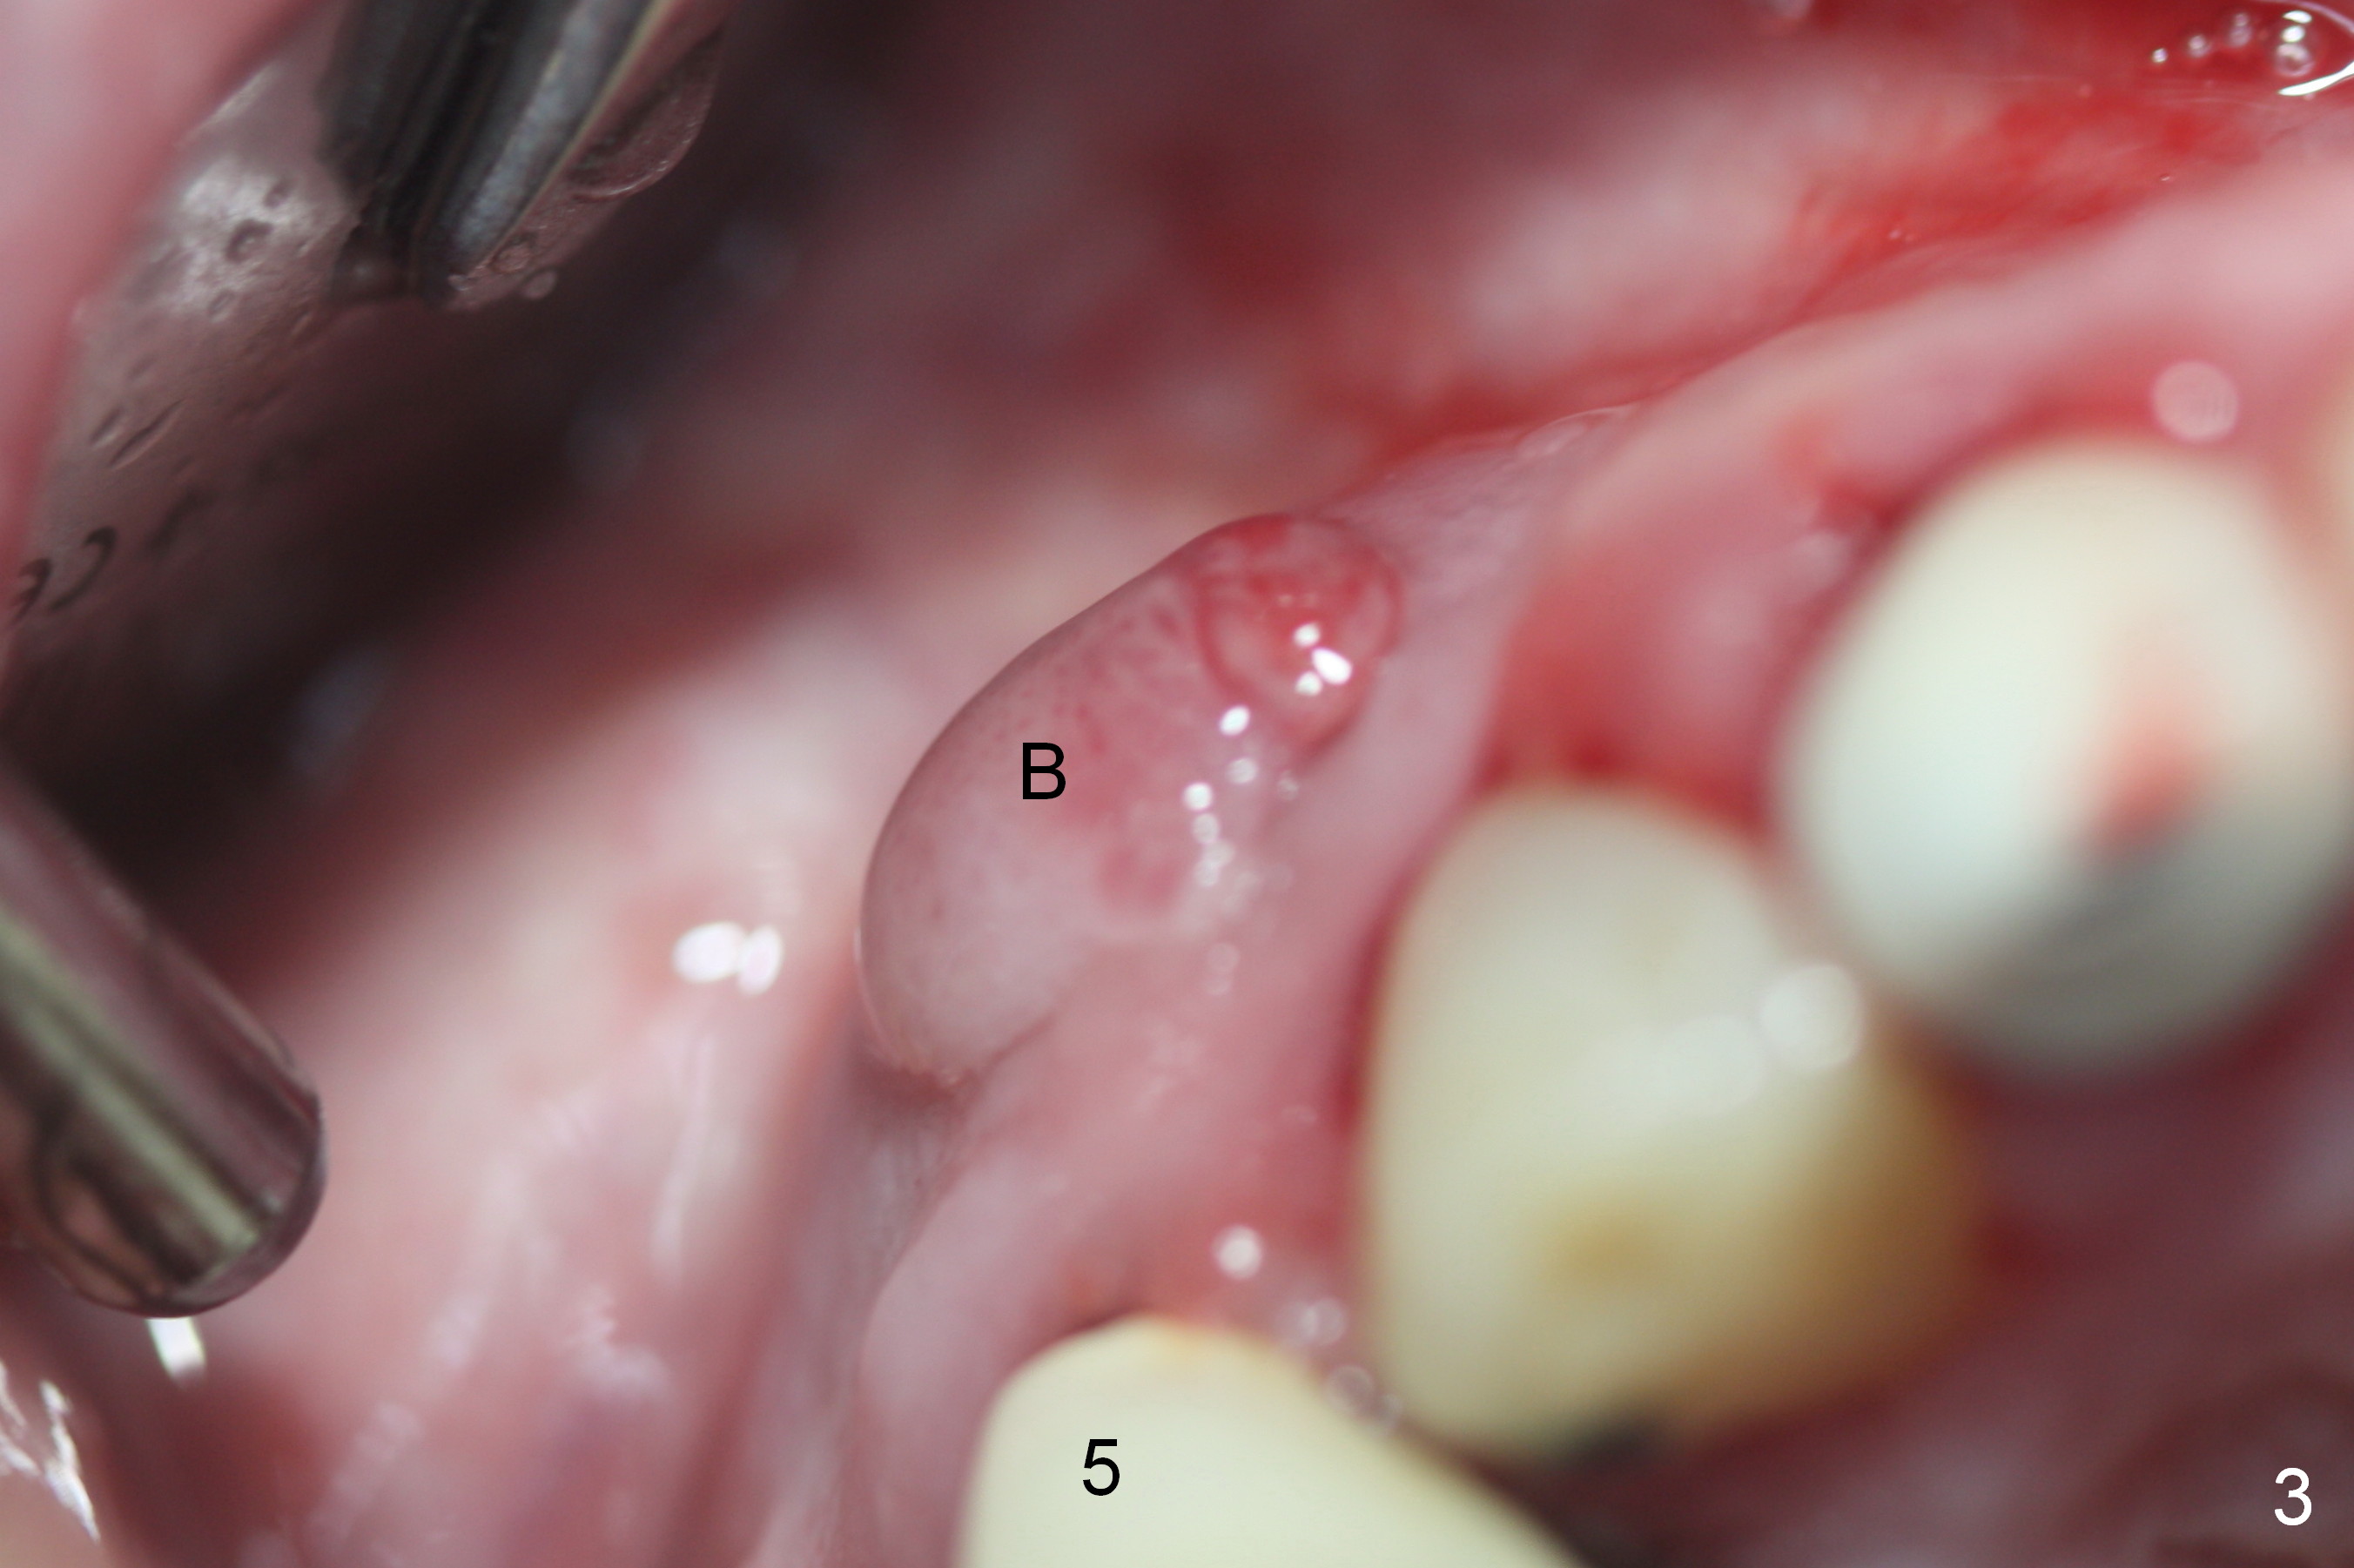

Preop photos show generalized gingival hyperplasia (hypertension med (Amlodipine, Calcium Channel Blocker), Fig.1 *), palatal (Fig.2<) and buccal (Fig.3 B) abscesses originated from the tooth #5. There is a smaller abscess buccal to the tooth #3 (not shown). After extraction, the buccal and palatal plates of the teeth #3 and 5 are found basically non-existent. When taps are placed, large socket defects are evident (Fig.4 *). In addition to sinus lift at #3 (Fig.5 black *), mineralized cancellous and cortical allograft (.5-1 and 1-2 mm) is placed around the implants with healing screws in place (white *). After the healing screws are removed and cemented abutments are placed, more allograft is packed (Fig.6-8 *). Closing the "dead" space in step may prevent immediately postop infection and peri-implantitis.